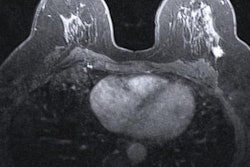

Breast cancer in women has surpassed lung cancer as the most commonly diagnosed type of cancer worldwide, according to a new report published February 4 in CA: A Cancer Journal for Clinicians.

The numbers highlight the importance of early detection, researchers said.

Female breast cancer has now exceeded lung cancer as the leading cause of global cancer incidence in 2020, and it is the fifth leading cause of cancer mortality around the world, the report authors found. Breast cancer ranks first for incidence in 159 out of the 185 countries included in the report.